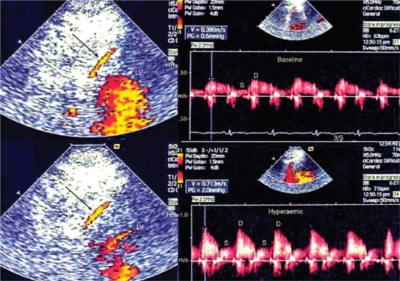

În aceasta fază diagnosticul se pune strict pe examenul ecografic. Examinarea ecografică în acest moment confirmă prezenţa trombului cu măsurarea dimensiunilor trombului. Ecografia vasculară este o metodă neinvazivă, nedureroasă, cel mai frecvent utilizată în diagnosticul TVP. După plasarea de gel special pe pielea membrului afectat, medicul urmăreşte cu ajutorul unui transductor pe ecranul ecografului anatomia sistemului venos, permeabilitatea acestuia, prezenţa fluxului sângelui şi a eventualelor cheaguri.

Repetarea ecografiei Doppler venoase este metoda de elecţie în urmărirea trombozei venoase profunde, în vederea stabilirii evoluţiei trombozei la nivelul sistemului venos profund, a gradului de obstrucţie al fragmentelor de venă afectate şi tratamentului.